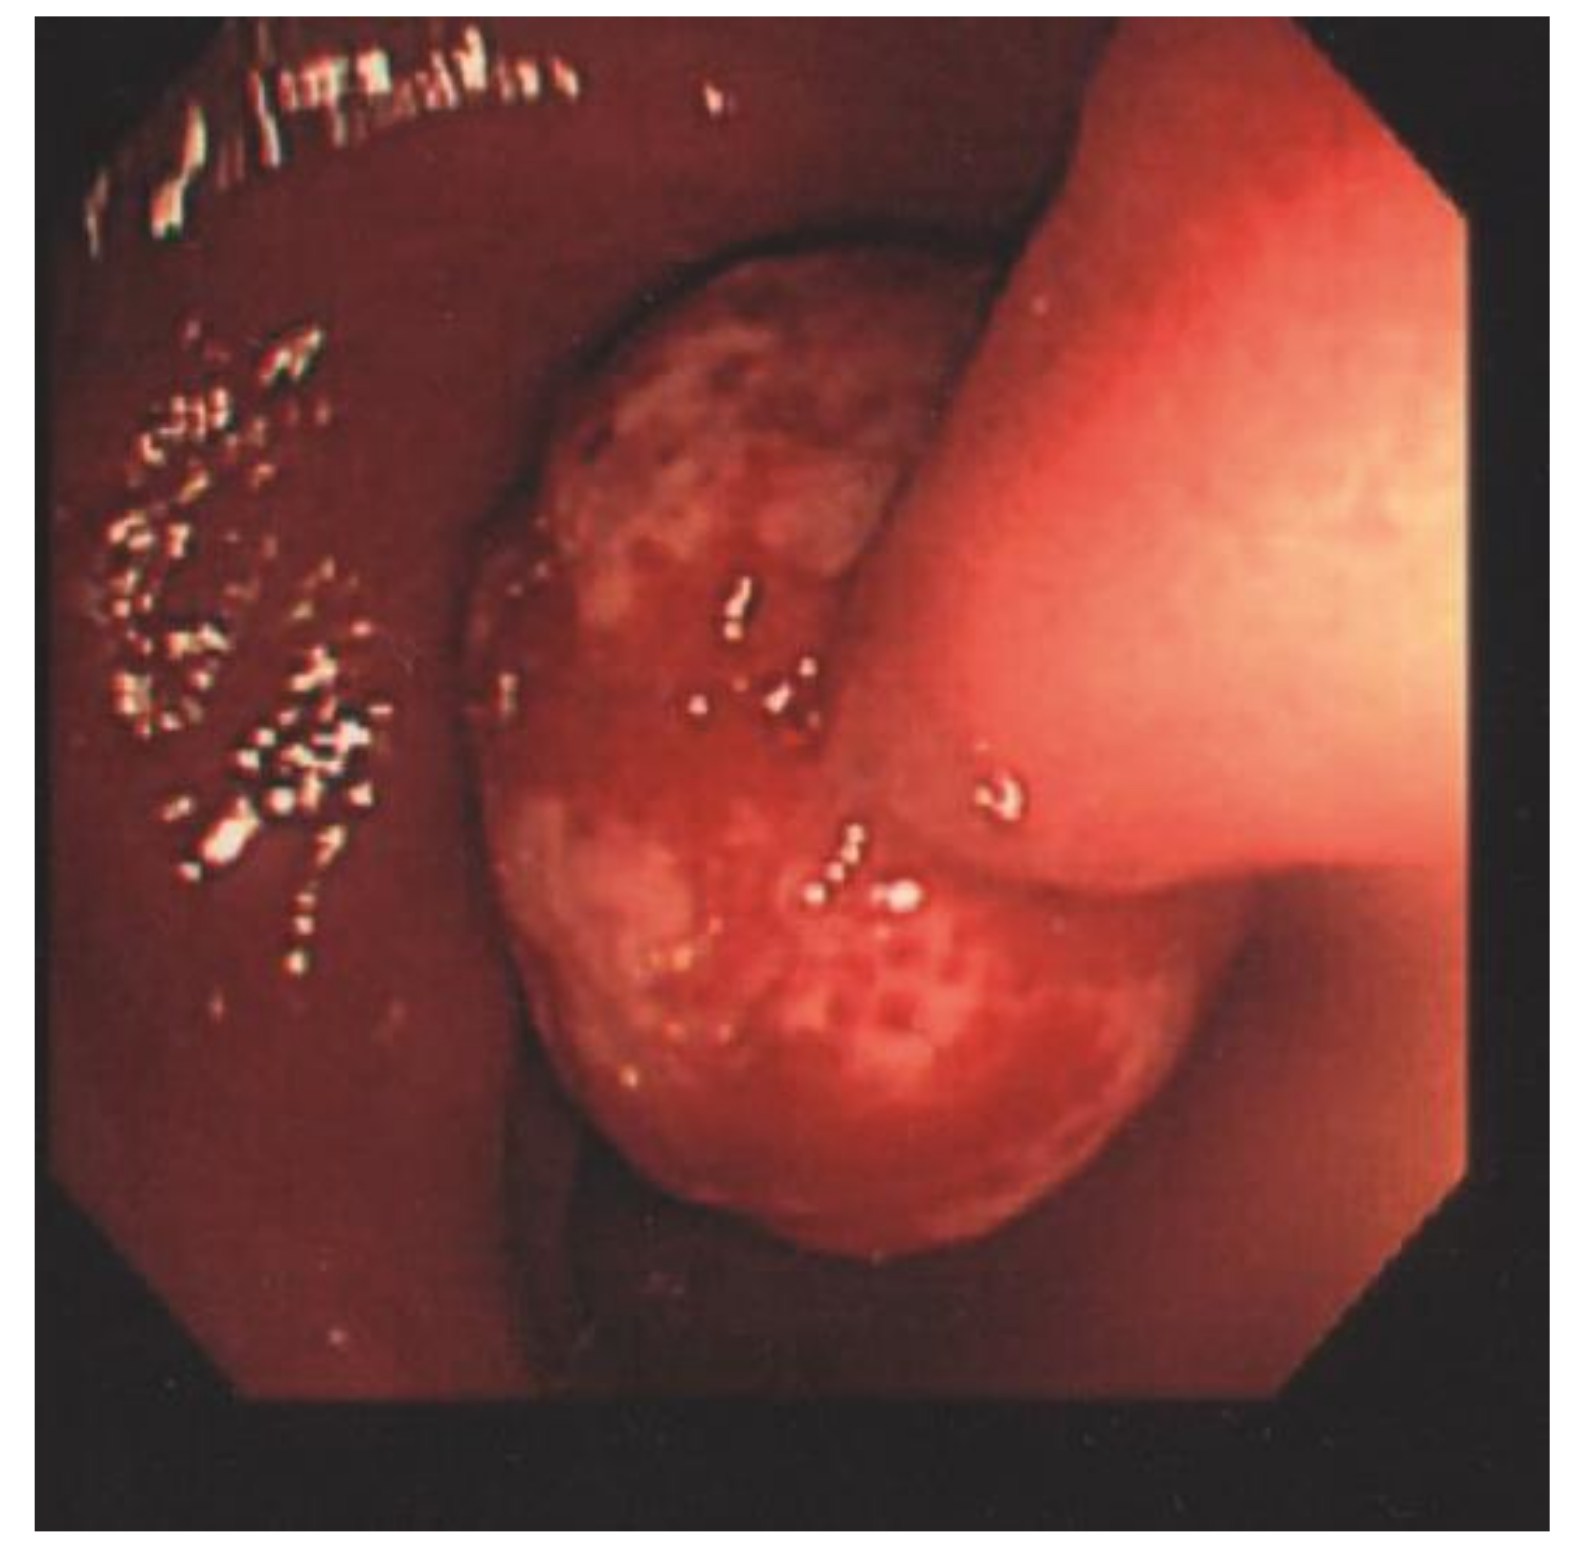

Endoloop-Assisted Polypectomy for a Symptomatic Giant Colonic Polyp in a Pediatric Patient

:1. Case Presentation